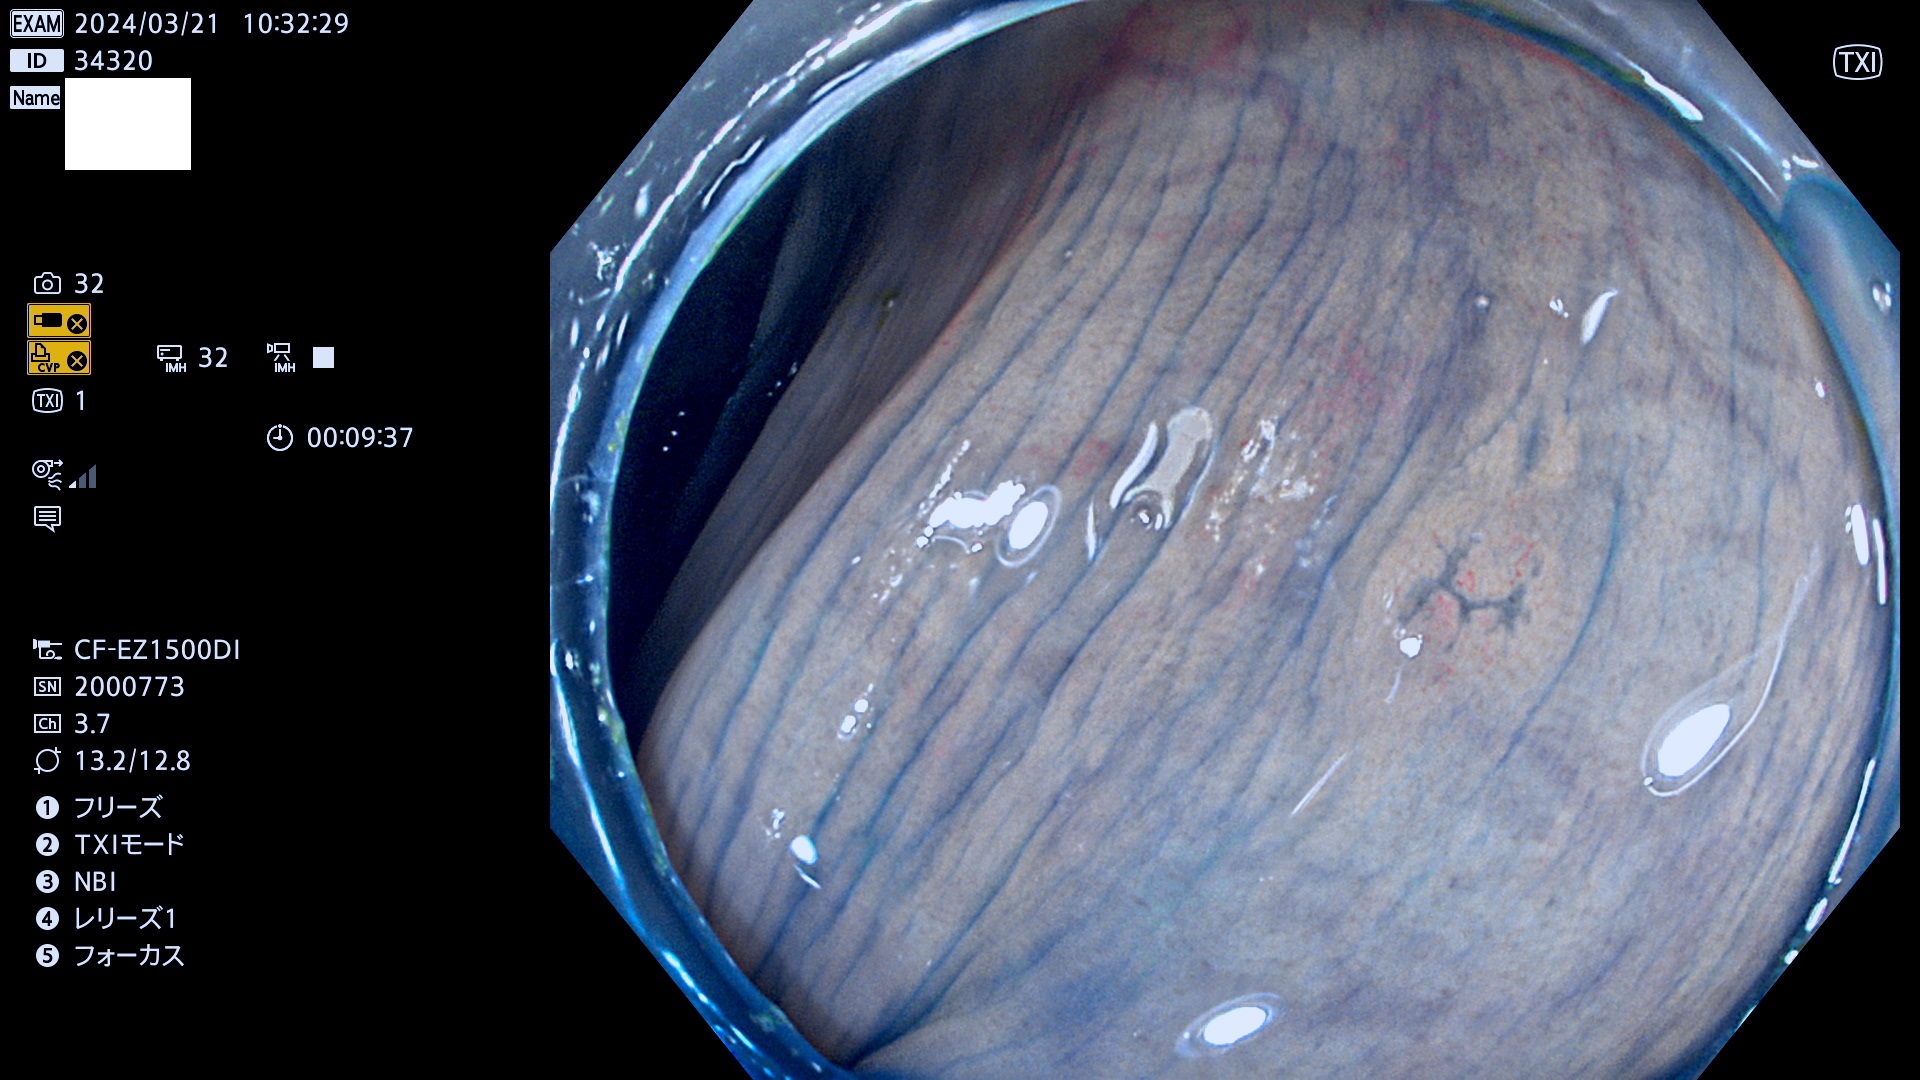

表面型腺腫(Flat Adenoma)の中で、完全に平坦な物をUb、陥凹している物をUcと呼びます。平坦隆起型(Ua)よりも、発見が難しく危険な病変です。

毎週の検査(木・金・土・日)に発見されたUb、Uc型・腺腫を、その週の日曜の夜にUPし1週間、提示します。

抽出の対象期間 2024年3月21日(木)〜3月24(日)の4日間(44件の検査)7件 (8/44=18%)